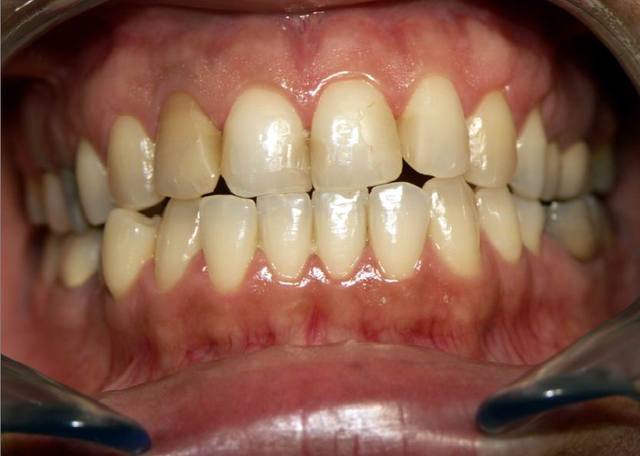

Autre cas .........d occluso.

Pour le cas d occluso ..........

Patiente de 43 ans soufrant de coxo-arthrose handicapante depuis + 10 ans. Douleurs permanente, agravée par la station debout.

Sur avis de son medecin, a refusé de se faire operer suite echec aux traitements medicaux.

1 ere seance de meulages mardi 1/2/05. Disparition de ses douleurs permanentes. Sensation de relachement et de dentente musculaire surtout au niveau des hanches.

2e senace aujourd hui. Pas de recidive au niveau des hanches, mais douleur cervicale et craquement ATM....deviation de la Md à l'ouverture....observable sur la photo 2

Meulages des dents marquées en bleu.

Disparition de la douleur cervicale en fin de meulage.

Persistance de craquement ATM et de deviation de la Md.

Prochaine seance mardi prochain.